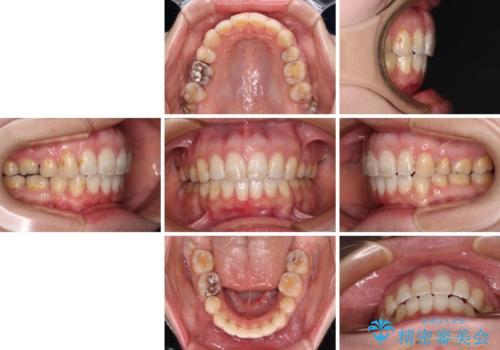

積極的に前歯を牽引したことで、口元の閉じにくさは顕著に改善され、横顔のシルエットが大幅に変化しました。

- 口元の閉じにくさと、前歯のでこぼこの歯並びを気にして来院された患者様です。

口元を積極的に引っ込めるために、上下左右の小臼歯計4本を抜歯することとしました。

セオリーでは第一小臼歯を抜歯しますが、上下右側は第二小臼歯に銀歯が装着されているため、第二小臼歯を抜歯することとしました。

上下正中を左右対称に揃えるため、アンカースクリューや補助装置を使用しながら口元を下げていくこととしました。